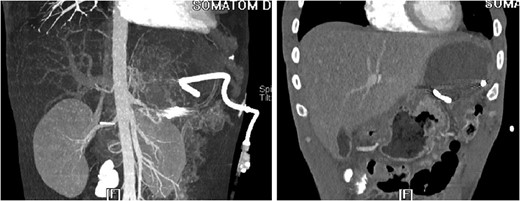

3D reconstruction and coronal CT after placement of pigtail drainage catheter.

The ‘Islands’ of preserved spleen lit up with IV contrast surrounded by a large collection of old blood and devitalized tissue.